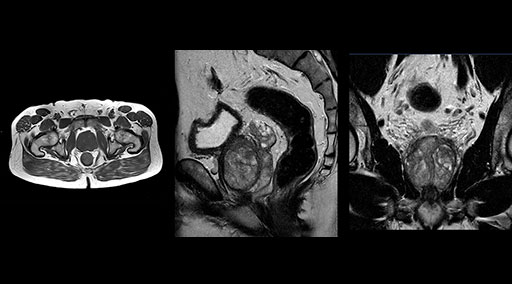

Patrick Duffy BS, RT (R) MR is Lead Technologist at DMG. “We are getting phenomenal image quality on all types of exams,” he says. “Our MSK is stellar, and so is our abdominal work. Ingenia excels at feet, hands and fingers. We do enterographies with great results. With the combination of the 3.0T magnet and the digital coils, we are able to scan prostates without an endorectal coil while still obtaining high quality results. This is a comforting experience for our male patients. We scan many obese patients, and the Ingenia does a tremendous job because of MultiTransmit, which reduces dielectric shading for more confident diagnosis. Our technologists really enjoy scanning on the Ingenia. We also have ordering physicians who specifically want their patients scanned on the Ingenia because of the results of our imaging.

“Without using an endorectal coil we do our prostate MR at 0.5 mm resolution, following the European society of urology protocol [1]. For certain joints we use a virtual arthroscopy protocol with 1 mm pixel size and 2 mm slice thickness. Ingenia really excels in our neurography, brachial plexus and prostate scans. Our neurologists insist on using our 3.0T for those,” Dr. Kaakaji adds.